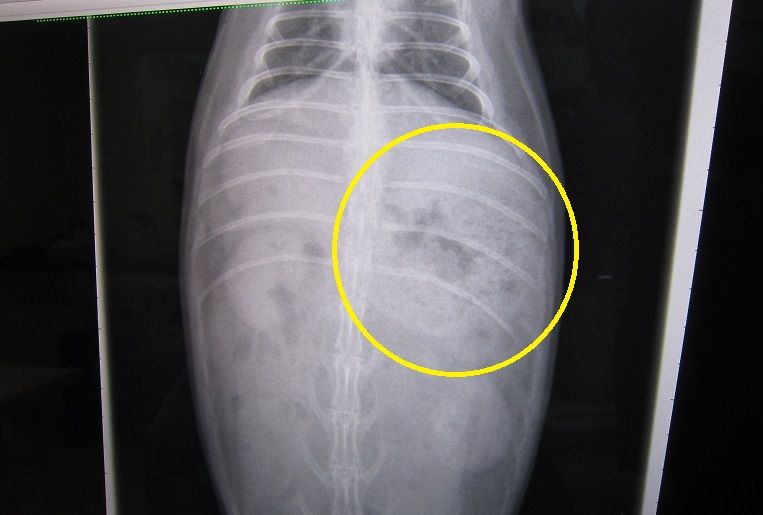

昨夜からの流れを話しし、診察、レントゲン

閉塞所見はありません

もちろん心臓も小さくなってないし

若干のガスはあれど、強いて指摘するならばレベル

で、ちゃんと出番待ちしとる(。・m・)

いつも感心するウンコ影“〆( ̄▽ ̄*)

と、胃腸に大きな問題はなさげだったのだが…

脂肪、すご過ぎやん…( ̄ェ ̄;)

前回との比較…